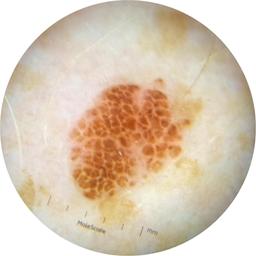

ISIC_3176953

diagnosis_1 Malignant

diagnosis_2 Malignant adnexal epithelial proliferations - Follicular

diagnosis_3 Basal cell carcinoma

image_type dermoscopic